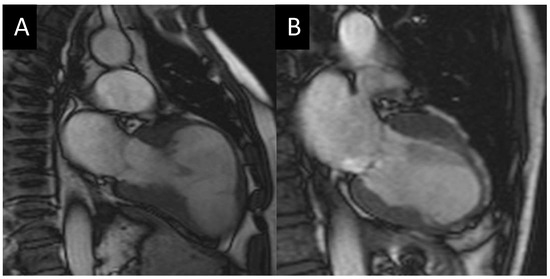

- Kwon, D.H.; Halley, C.M.; Carrigan, T.P.; Zysek, V.; Popovic, Z.B.; Setser, R.; Schoenhagen, P.; Starling, R.C.; Flamm, S.D.; Desai, M.Y. Extent of left ventricular scar predicts outcomes in ischemic cardiomyopathy patients with significantly reduced systolic function: A delayed hyperenhancement cardiac magnetic resonance study. JACC Cardiovasc. Imaging 2009, 2, 34–44. [Google Scholar] [CrossRef] [PubMed]

- Dor, V.; Saab, M.; Coste, P.; Kornaszewska, M.; Montiglio, F. Left ventricular aneurysm: A new surgical approach. Thorac. Cardiovasc. Surg. 1989, 37, 11–19. [Google Scholar] [CrossRef] [PubMed]

- Isomura, T.; Hoshino, J.; Fukada, Y.; Kitamura, A.; Katahira, S.; Kondo, T.; Iwasaki, T.; Buckberg, G.; Group, R. Volume reduction rate by surgical ventricular restoration determines late outcome in ischaemic cardiomyopathy. Eur. J. Heart Fail. 2011, 13, 423–431. [Google Scholar] [CrossRef]

- Castelvecchio, S.; Menicanti, L.; Ranucci, M.; Di Donato, M. Impact of surgical ventricular restoration on diastolic function: Implications of shape and residual ventricular size. Ann. Thorac. Surg. 2008, 86, 1849–1854. [Google Scholar] [CrossRef]

- Secchi, F.; Nardella, V.G.; Giardino, A.; Di Leo, G.; Castelvecchio, S.; Menicanti, L.; Sardanelli, F. Atypical myocardial delayed enhancement after surgical ventricle restoration. Eur. J. Radiol. 2012, 81, e292–e297. [Google Scholar] [CrossRef]

- Castelvecchio, S.; Careri, G.; Ambrogi, F.; Camporeale, A.; Menicanti, L.; Secchi, F.; Lombardi, M. Myocardial scar location as detected by cardiac magnetic resonance is associated with the outcome in heart failure patients undergoing surgical ventricular reconstruction. Eur. J. Cardiothorac. Surg. 2018, 53, 143–149. [Google Scholar] [CrossRef]

- Solowjowa, N.; Nemchyna, O.; Hrytsyna, Y.; Meyer, A.; Hennig, F.; Falk, V.; Knosalla, C. Surgical Restoration of Antero-Apical Left Ventricular Aneurysms: Cardiac Computed Tomography for Therapy Planning. Front. Cardiovasc. Med. 2022, 9, 763073. [Google Scholar] [CrossRef]